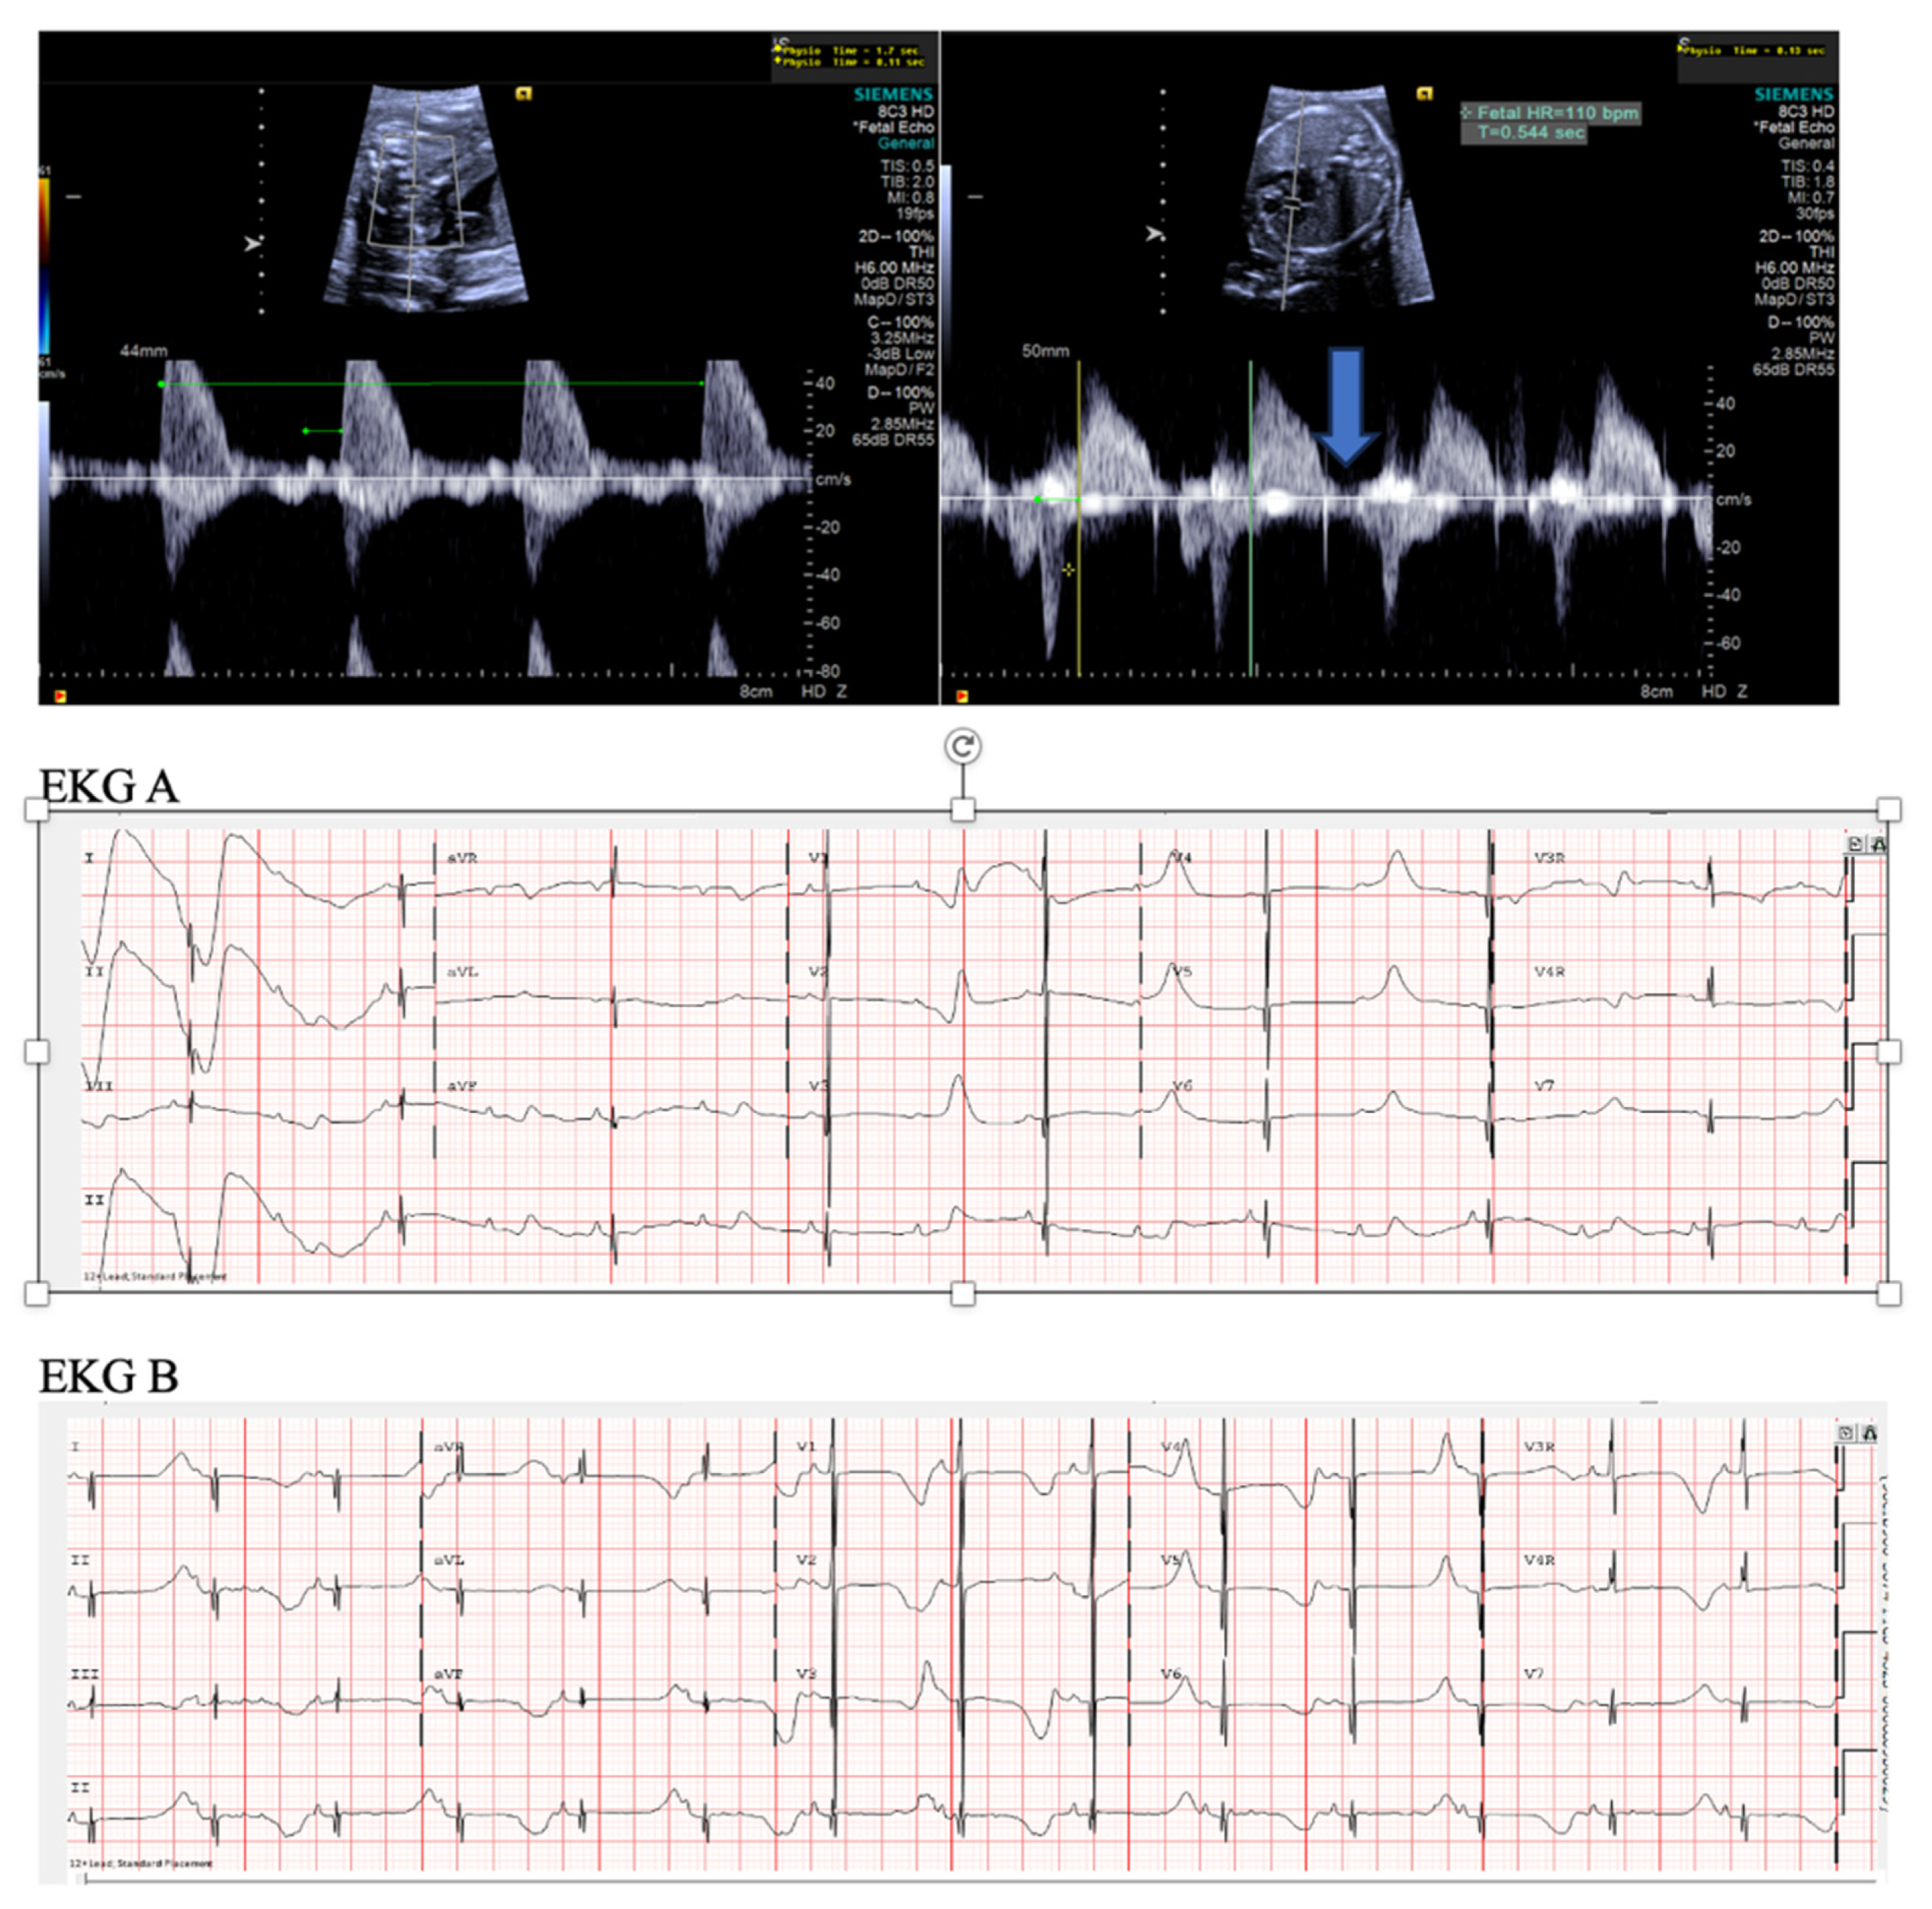

- Short VA SVT (Figure 3 and Figure 4) demonstrates a ventricular–atrial (VA) interval that is less than half of the ventricular–ventricular (VV) interval (VA:AV ratio < 1) and a sudden onset and termination of tachycardia; tachycardia usually terminates with a non-conducted atrial contraction. Short VA SVT includes AVRT (also known as orthodromic reciprocating tachycardia, ORT) and atrioventricular nodal reentrant tachycardia (AVNRT). Short VA SVT typically presents after 18 weeks of gestation.

- Long VA SVT (Figure 4) demonstrates a VA interval that is more than half of the VV interval (VA:AV ratio > 1). Long VA SVT includes EAT and PJRT. A distinguishing feature of EAT is tachycardia termination with ventricular contraction. Long VA SVT may occur as early as 12 weeks of gestation. Because long VA tachycardias have slower rates, they are less likely to cause hydrops.